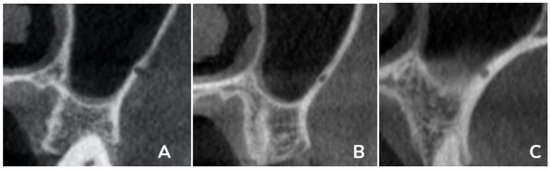

Diseases and pathologies in the maxillofacial region are functional and aesthetic challenges for patients. However, the anatomy in the maxillofacial region is complex, and dentists and maxillofacial surgeons rely on good imaging tools for accurate diagnosis and the management of these conditions. Cone-beam computed tomography (CBCT), as an alternative to traditional computed tomography, offers a cheaper option requiring a lower dose of radiation, while providing good image quality, and has been a workhorse for the oral and maxillofacial imaging of hard tissue. The versatility and small space occupancy of a CBCT allow a clinic-based setup that improve access and popularize its usage.

The scope of the use of CBCT in the maxillofacial region ranges from simple oral surgery to complex maxillofacial deformities, diseases and trauma. Considerations and applications of CBCT in various anatomical spaces and clinical applications are of huge interest to practicing clinicians. Computer virtual planning and 3D printing based on CBCT images have further extended the clinical applications. Artificial intelligence can also use the data acquired from CBCT for the automated detection and diagnosis of disease conditions through machine- and deep-learning algorithms.